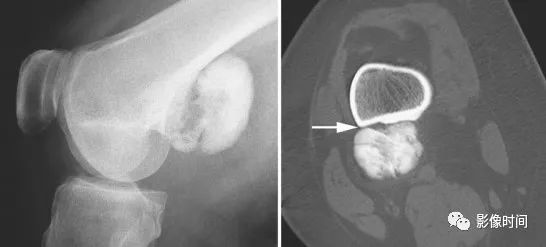

(一)瘤软骨钙化:瘤软骨常表现为环状钙化, 是诊断软骨类肿瘤较为可靠的影像学征象。环状钙化形成于环状软骨、以及软骨小叶边缘的软骨基质。钙质沉着可呈小点状、小条状、半环状或弧形;亦可浓密相连、重叠呈菜花状。钙化环的形态和密度可反映瘤组织分化程度, 通过观察钙化环的形态和密度,有助于良恶肿瘤的鉴别。

良性瘤软骨之瘤细胞分化好、生长缓慢、血供充分, 钙化环完整,密度高, 边缘清楚。良性软骨类肿瘤如骨软骨瘤(图 35)、软骨母细胞瘤(图 36)、内生软骨瘤(图 37)等均可于瘤组织内发生环形钙化。

恶性瘤软骨则呈密度淡薄, 边缘模糊的不规则钙化,恶性骨肿瘤的环形钙化,最多见于软骨肉瘤(图 38),其次是骨肉瘤。CT 是发现肿瘤内软骨钙化最为敏感的检查方法。

图 35  瘤软骨钙化:骨软骨瘤

图 36  瘤软骨钙化:软骨母细胞瘤

图 37  瘤软骨钙化:内生软骨瘤

图 38  瘤软骨钙化:软骨肉瘤